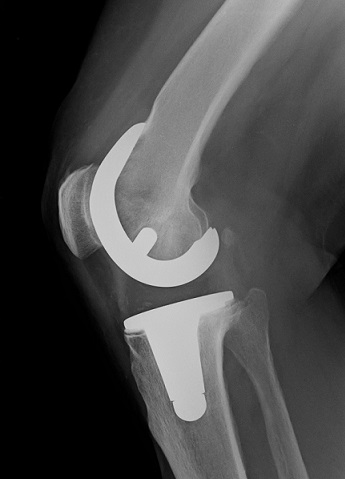

TEP_Knie_r